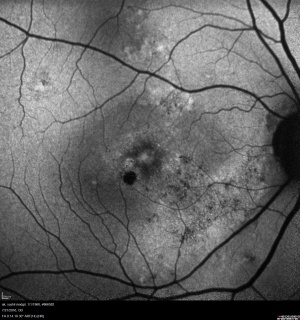

Retinal imaging techniques have evolved at a remarkable pace in the last two decades. Wide field imaging (WFI) and ultra wide field imaging (UWFI) are now increasingly popular. WFI refers to imaging beyond 50 degrees field area. UWFI systems can image upto 200 degrees as in Optos.[2] They are well capable of imaging over 80% of the retinal surface area. The peripheral retina can be photographed with small pupils[3][4] in instances where dilated peripheral fundus examination may be limited due to pupil size. Besides imaging, WFI also provides valuable information about the peripheral vasculature and other retinal lesions that might otherwise be missed with traditional imaging systems.

- Simultaneous imaging of central and peripheral retina; use of UWF FA to evaluate peripheral retinal ischemia in patients with diabetic macular edema and other vascular complications in the central macula

Applications of WFI and UWFI in Ocular Conditions

- Screening for diabetic retinopathy